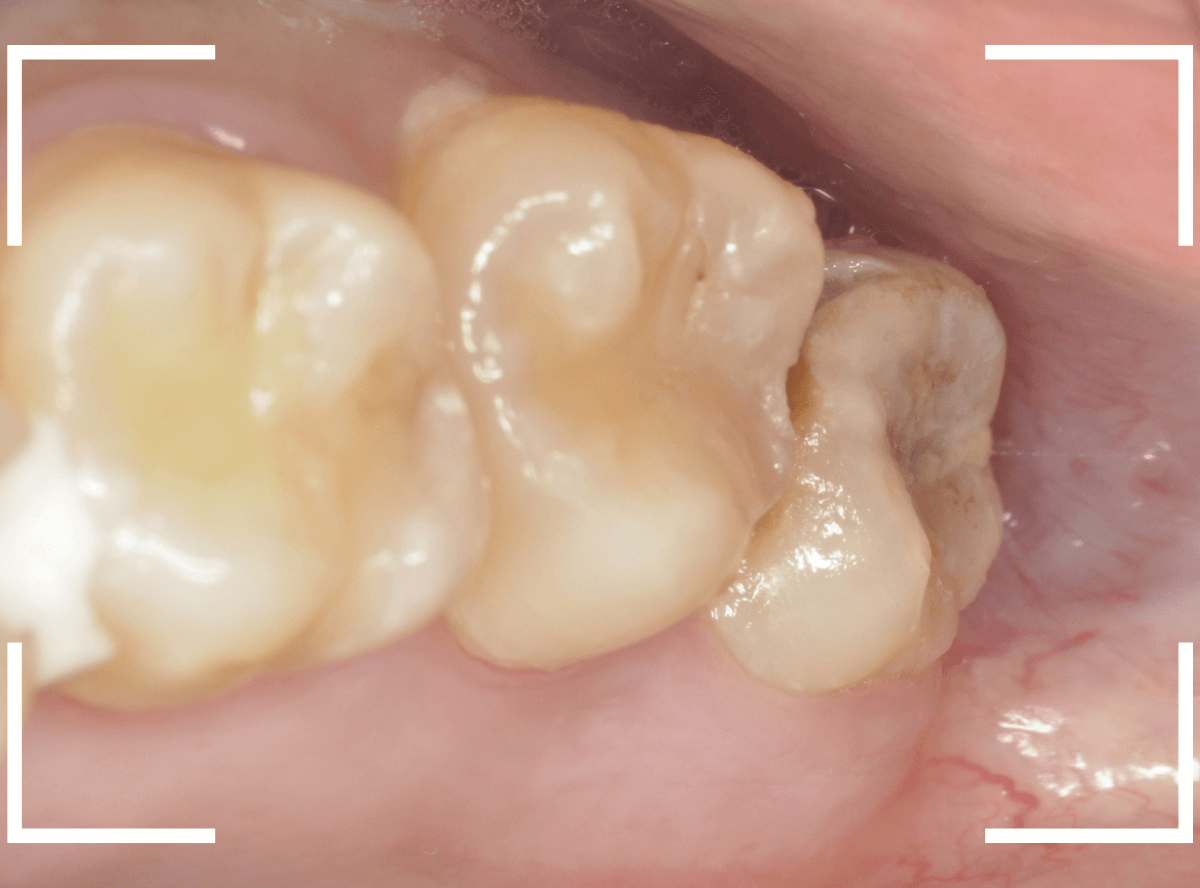

このようなおやしらず、あなたはありませんか?